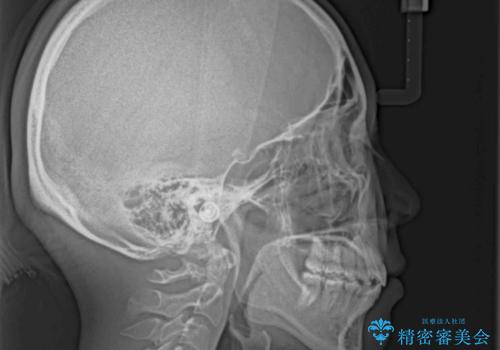

- 上の前歯の出っ歯とでこぼこの歯並びを気にして来院された患者様です。

口元を積極的に引っ込めるために、上下左右の小臼歯4本を抜歯することとしました。

4本の歯を抜歯したことで、飛び出していた口元が引っ込み、横顔が大きく改善されました。

咬み合わせが悪化することのないようにスペースを閉じていくことができ、比較的スムーズに治療を進めることができました。